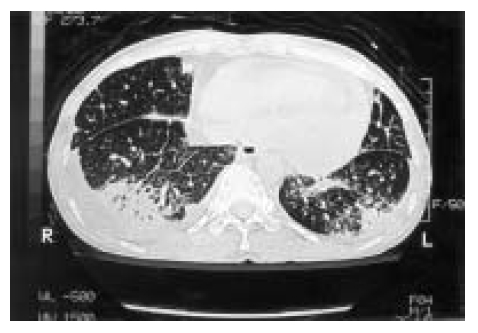

High-resolution computed tomography of the chest demonstrated bilateral consolidations in both lower lung zones, associated with bilateral pleural effusion and moderate amount of pericardial effusion (Figure 4).